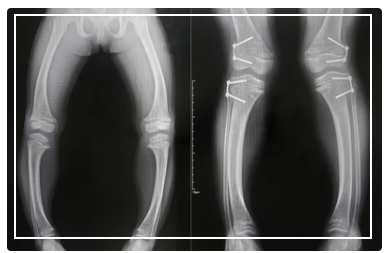

구루병은 비타민D 결핍으로 인해 뼈의 약화, 골격 변형 등이 나타나는 질환입니다.

주로 어린아이들에게 발생하며, 다리가 O자 모양으로 휘거나, 뼈가 약해져 골절 위험이 높아집니다.

비타민D가 부족하면 구루병이 발생할 수 있습니다. 구루병은 뼈의 약화, 골격 변형 등이 나타나는 질환입니다. 주로 어린아이들에게 발생하며, 다리가 O자 모양으로 휘거나, 뼈가 약해져 골절 위험이 높아집니다.